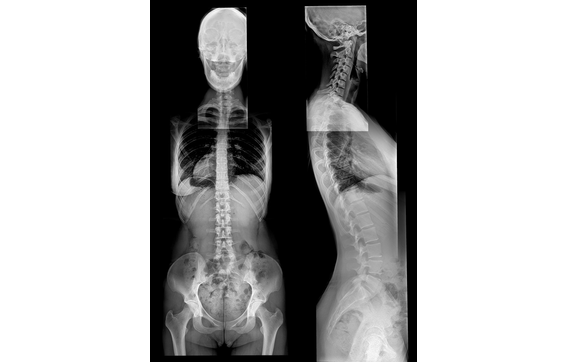

Full Spine X-Ray by Reformation Chiropractic

Full spine radiographs allow us to get a clear blueprint of your spine in order for us to get you the results you are looking for quicker and more ...